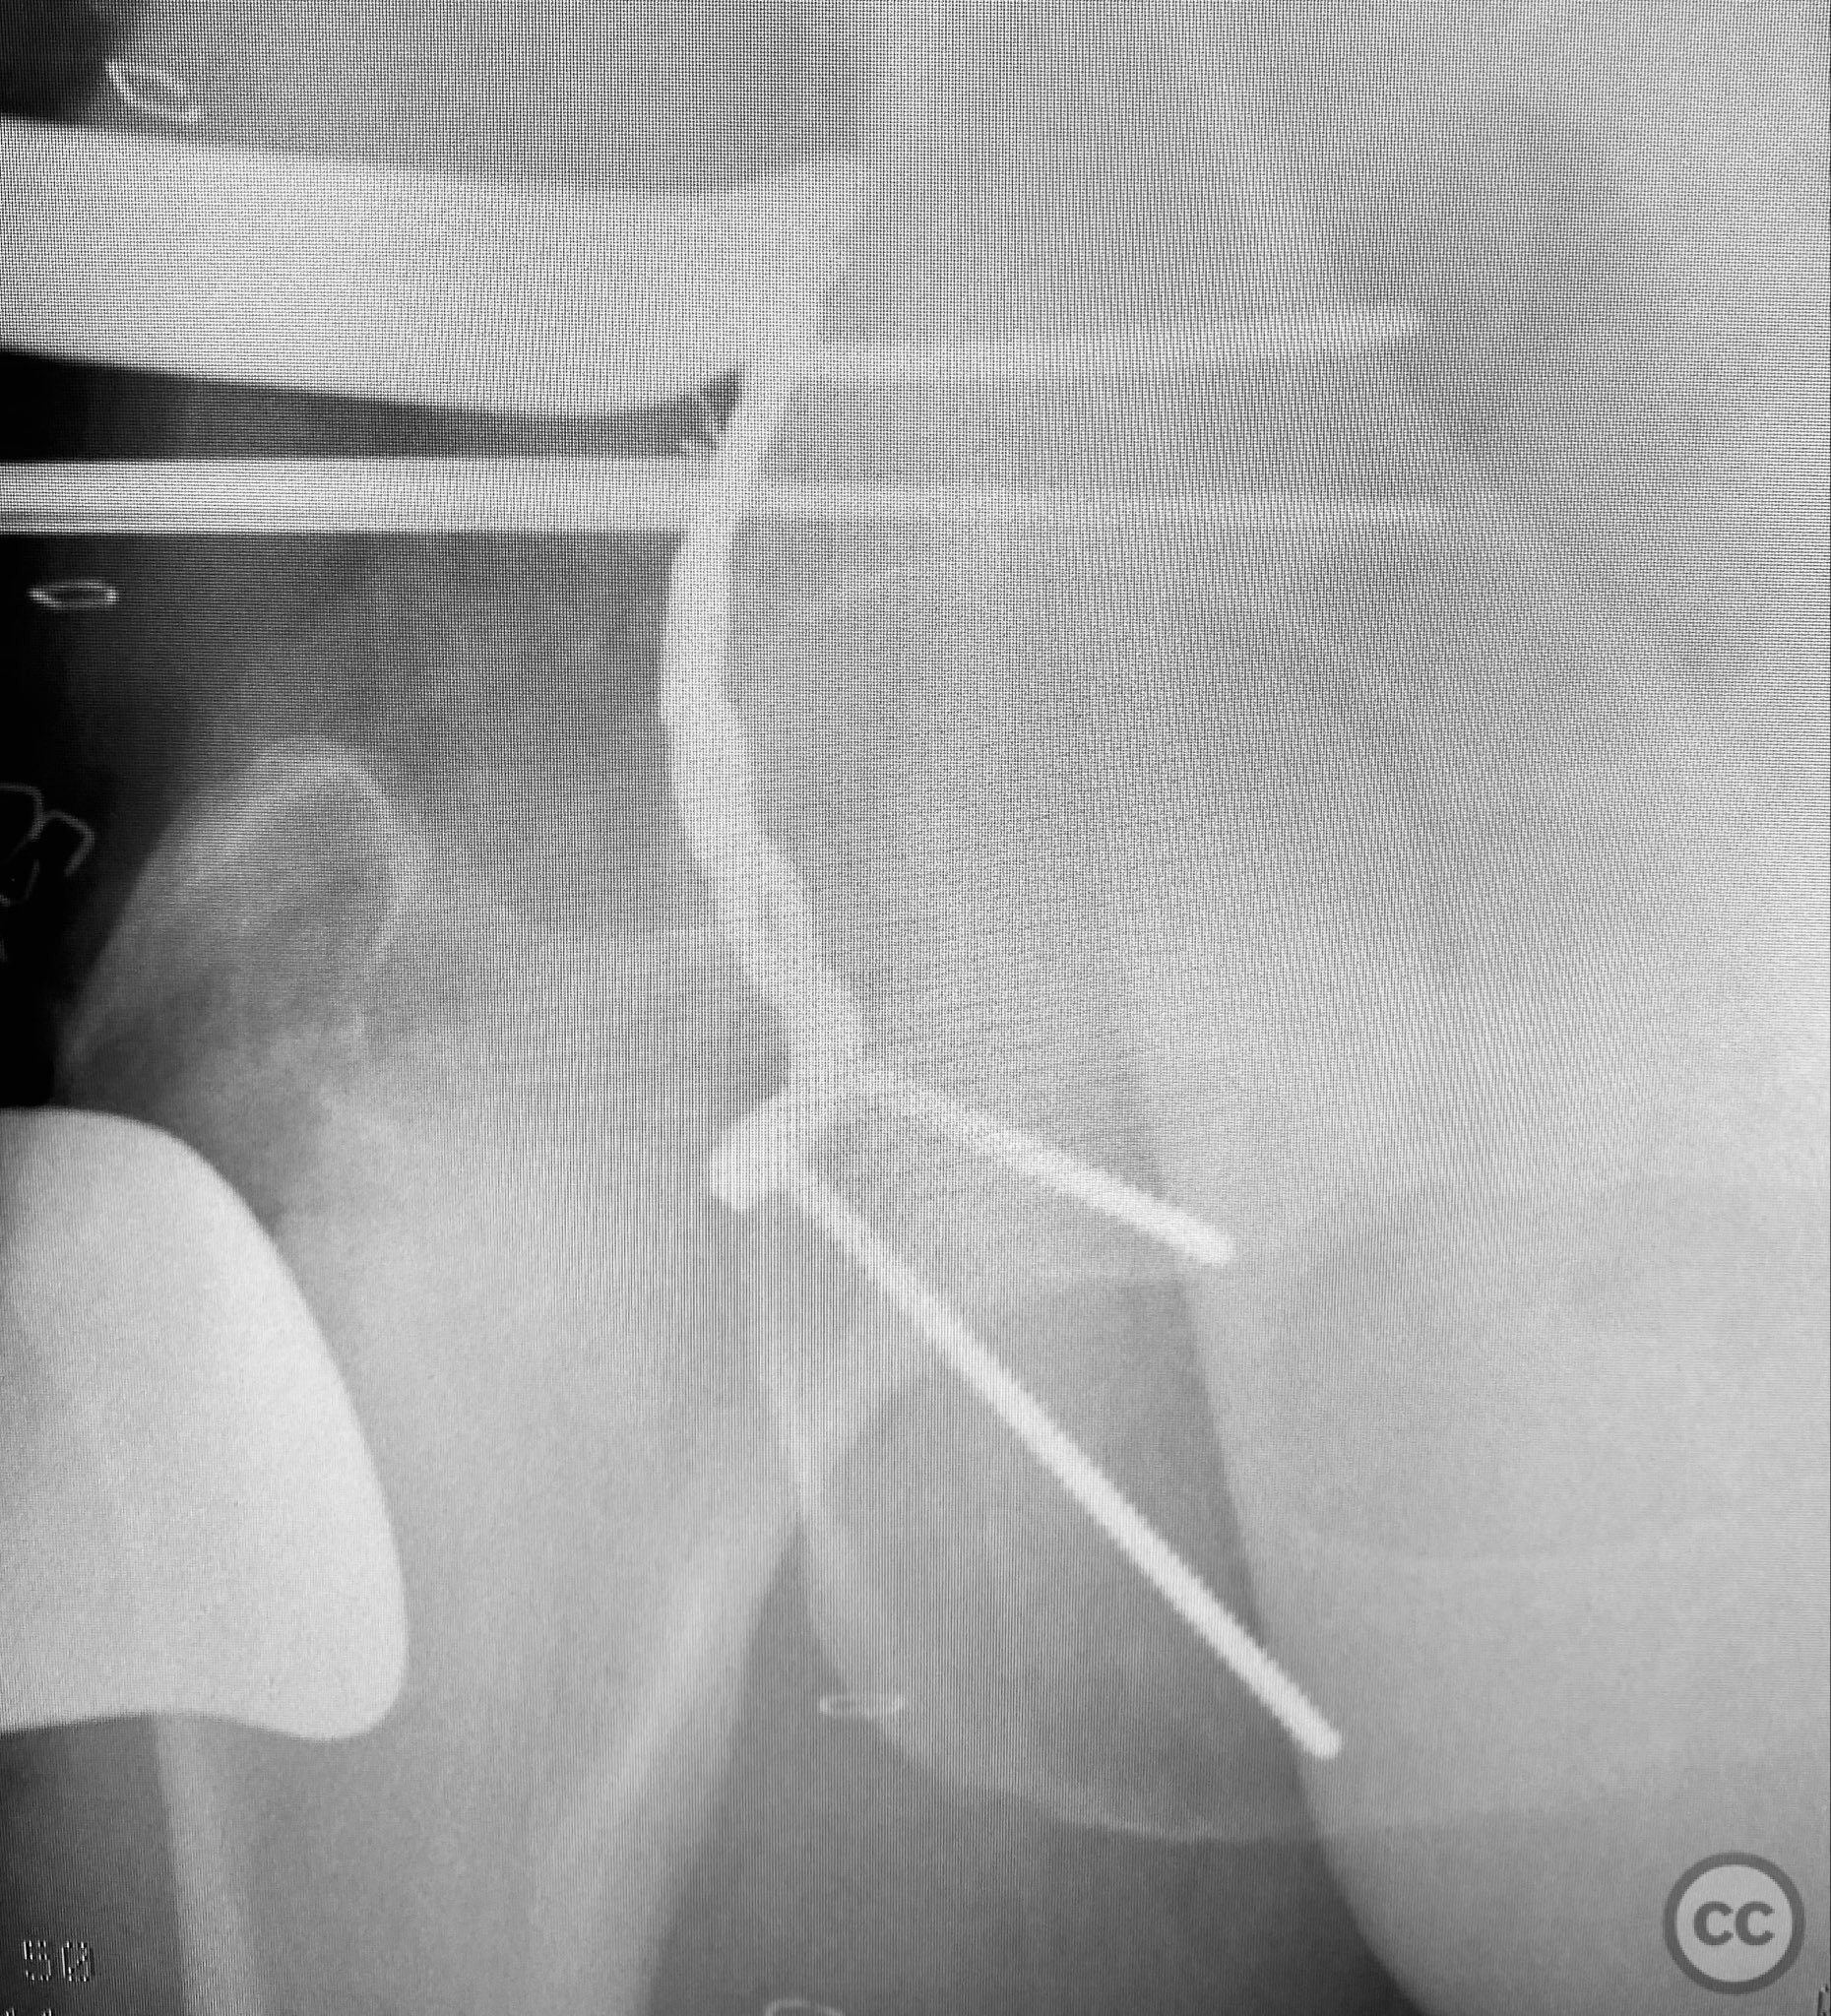

Intraoperatively, elevation and reduction of impacted articular fragments were performed, followed by bone grafting of subchondral defects. The posterior wall fragment was anatomically reduced and initially stabilized with a contoured plate. Intraoperative fluoroscopy (obturator oblique view) was utilized to guide placement of an additional screw through the plate above the joint, traversing both the posterior wall fragment and stabilizing the transverse fracture line. A supplementary medial plate was applied to further support both fracture components. Postoperative CT imaging confirmed satisfactory reduction of both the posterior wall and transverse fractures, as well as restoration of articular congruity in previously impacted areas. Consideration is given to whether initial reduction and lag screw fixation of the transverse component prior to plate application may have improved reduction; however, final imaging demonstrated acceptable alignment.

Patient positioning:  The patient was positioned prone on a radiolucent table to facilitate posterior pelvic access and intraoperative fluoroscopic imaging.